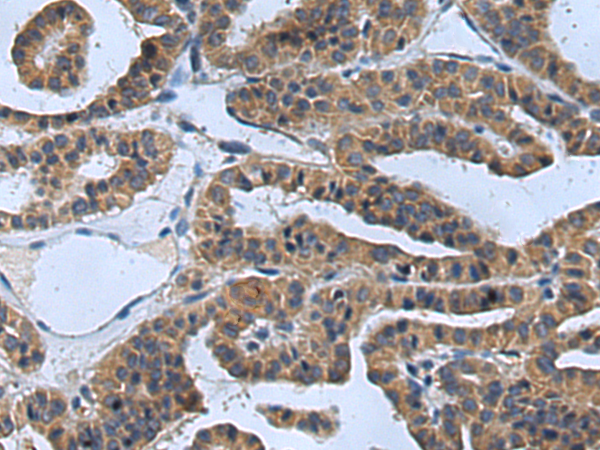

分类: 科研抗体货号: P08918别名: Ptg-2; TSC22; TGFB1I4应用: IHC反应种属: Human, Rat